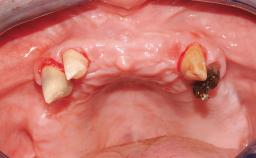

Immediate Loading of Eight Implants in the Maxilla and Six Implants in the Mandible and Final Restoration with Three-Unit and Four-Unit FDPs

German Gallucci, Jean-Pierre H Bernard, Urs C Belser

Extensive scientific evidence has confirmed that immediately loaded implants with fixed full-arch provisional restorations can osseointegrate with success rates similar to conventionally or delayed loaded implants. A number of immediate-provisionalization techniques for edentulous jaws have been described. Some protocols differ when it comes to prefabricated provisional templates versus complete denture conversion; intrasurgical impressions versus direct relining; and cemented versus screw-retained provisional restorations. In this context, complete-denture conversion has been proposed for either intrasurgical impressions or direct relining. Another possibility is the utilization of a prefabricated provisional to be adapted either in the mouth (by direct relining) or in the laboratory (on a working model obtained from an intrasurgical impression).

Case Type Edentulous Maxilla